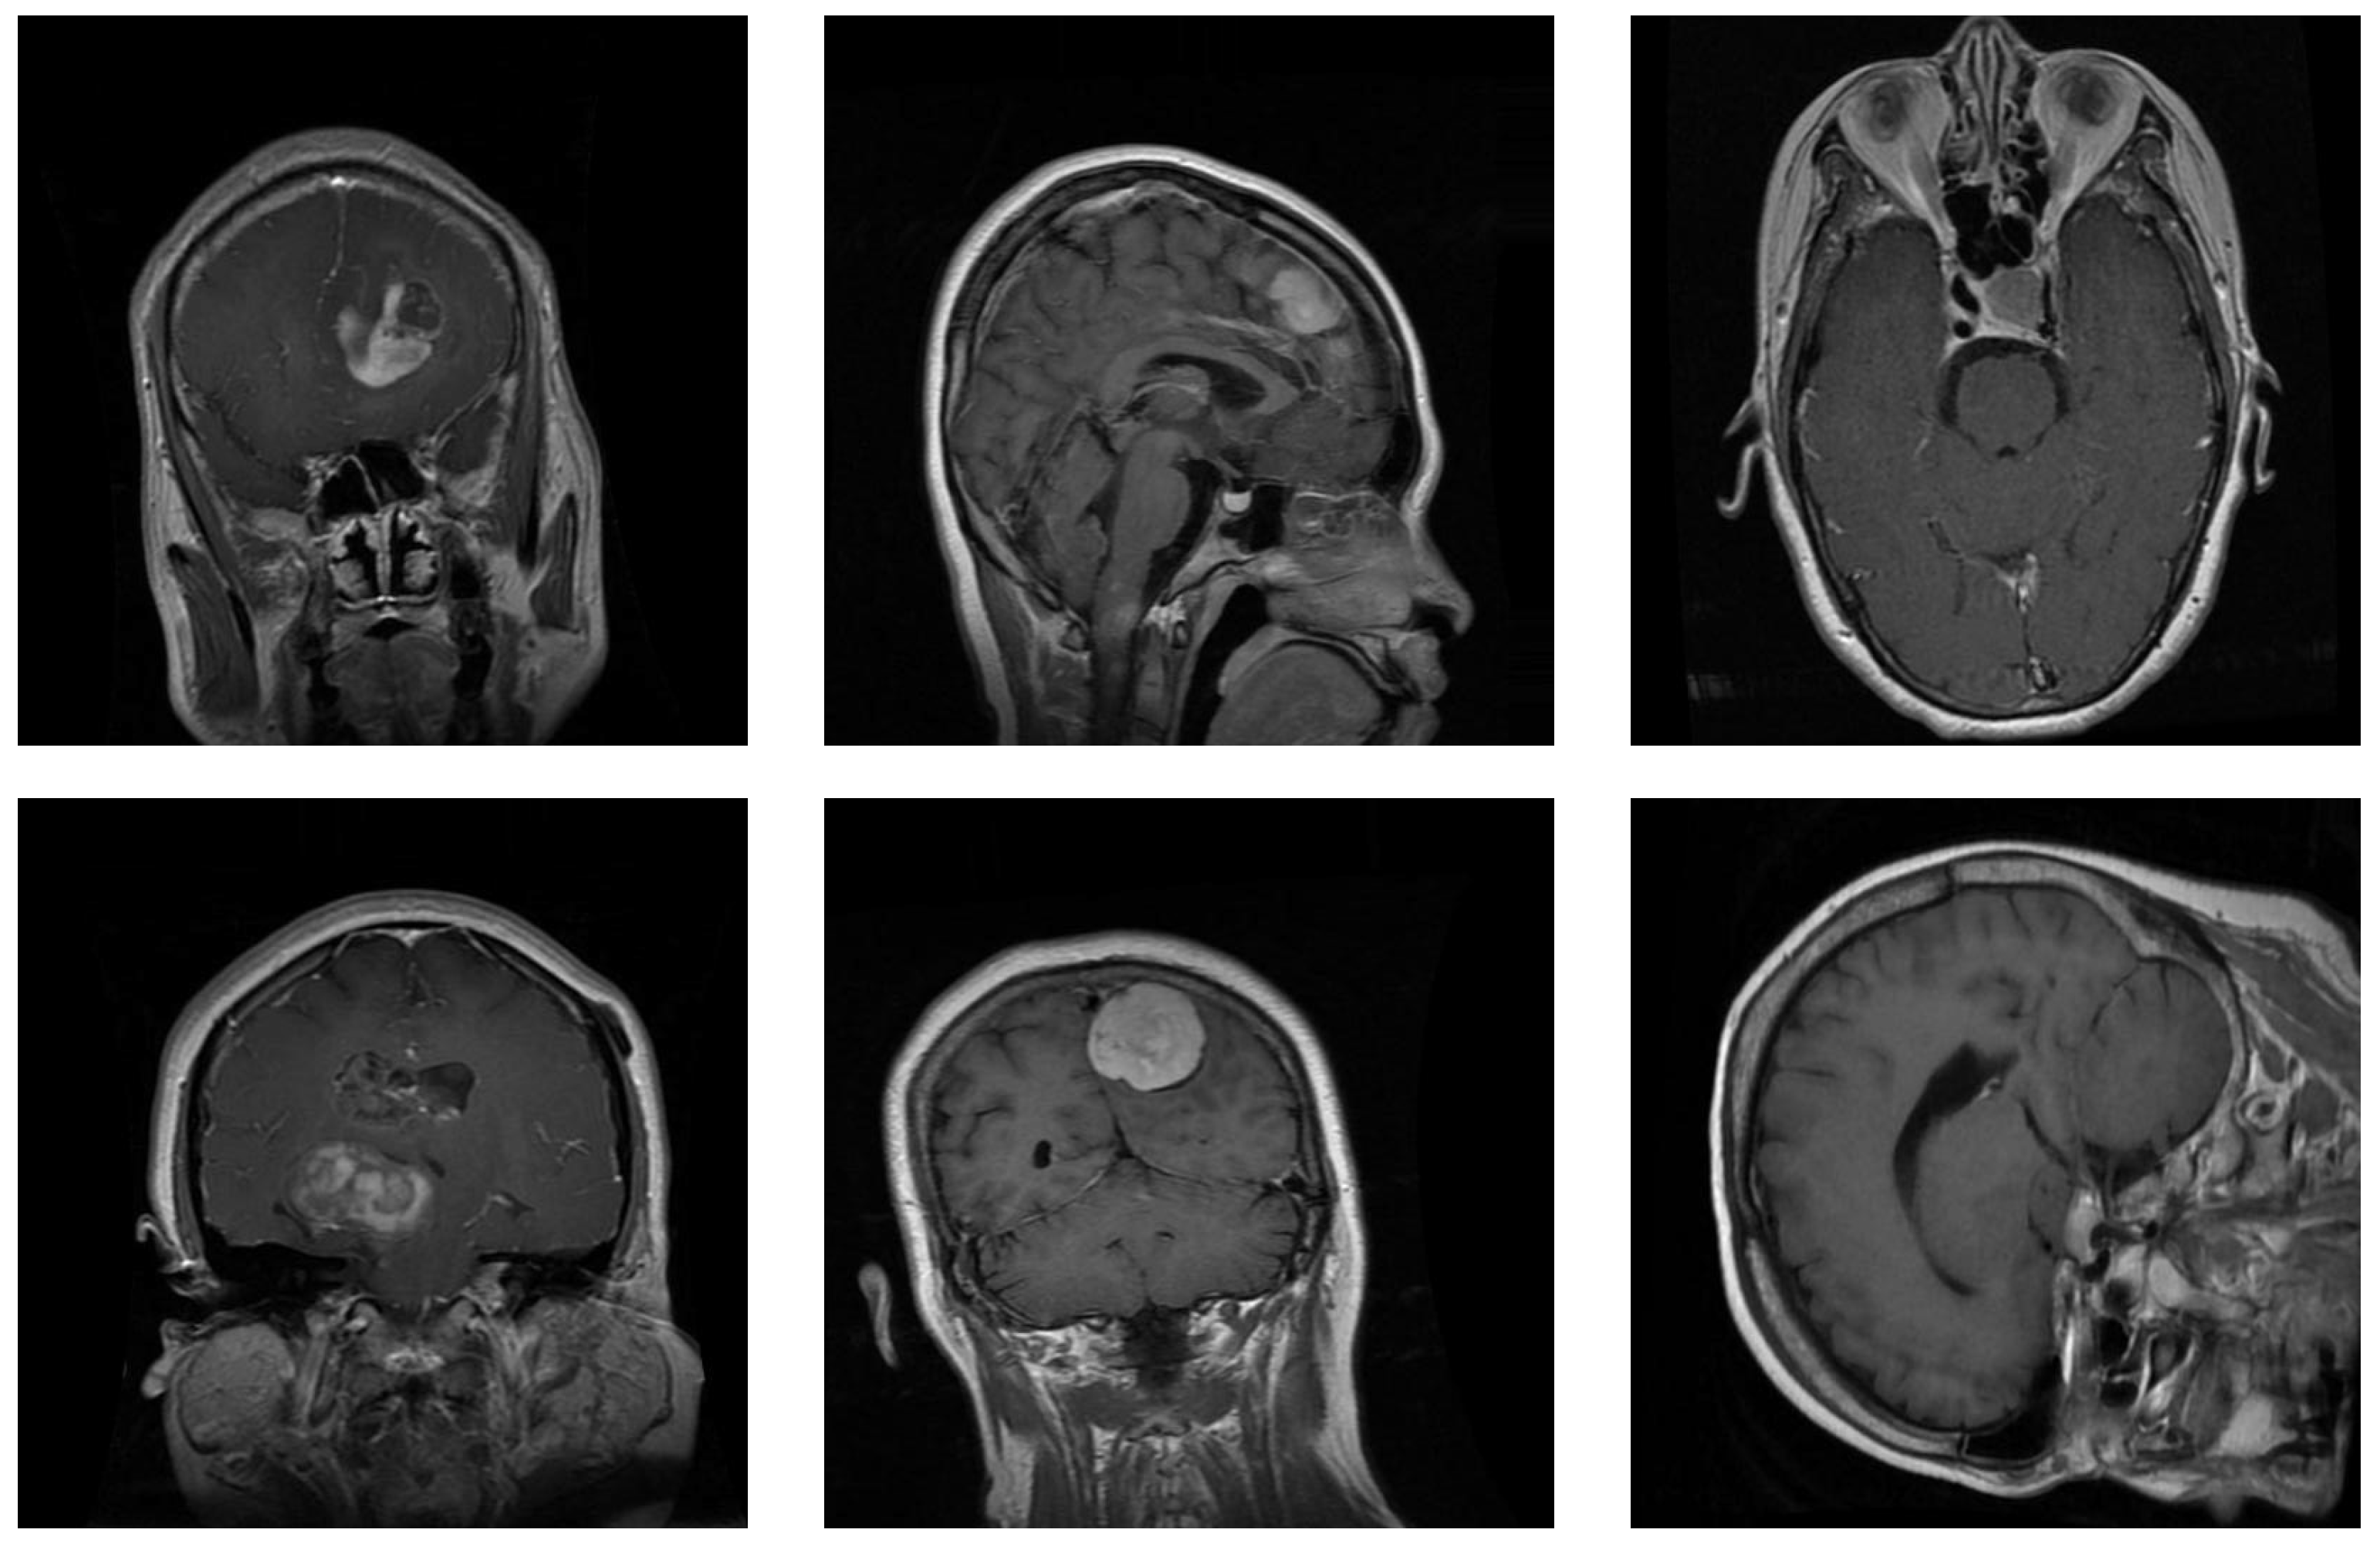

Figure 1 depicts several examples of brain tumors in the dataset. This dataset forms part of a larger collection that encompasses eight distinct cancer types from different organs: acute lymphoblastic leukemia, brain, breast, cervical, kidney, lung, colon, and oral cancer. The images are in JPEG format with dimensions of  pixels. We selected brain cancer, which contained the three previous tumor subclasses. Each subclass included the same number of images (5000 MRIs).

Figure 1.

Samples from the brain dataset: the first column shows two examples of glioma tumors; the middle column shows meningioma tumors; and the last column depicts images of pituitary tumors.